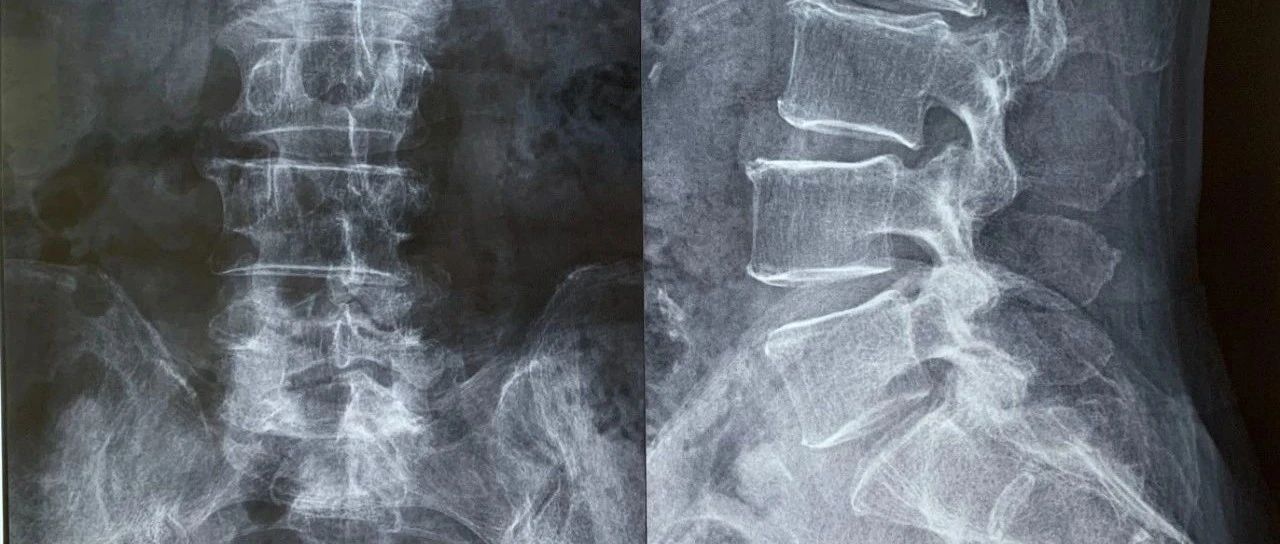

因腰背部疼痛就诊的患者,诊断为何?|病例分享

患者男性,61岁。主因腰背部疼痛于急诊就诊。

医脉通抗感染 2020-11-06